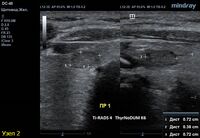

4) Узел правой доли, не прорастает капсулу щитовидной железы (0 баллов), больше широкий чем высокий (0 баллов), не имеет кальцинатов (0 баллов), с ровным четким контуром (0 баллов), изоэхогенный (1 балл), смешанной структуры (кистозно солидный) (1 балл). Количество баллов 2, ACRTi-RADS2, ThyrNoDUMК1. Пункция не показана в связи с низким риском.